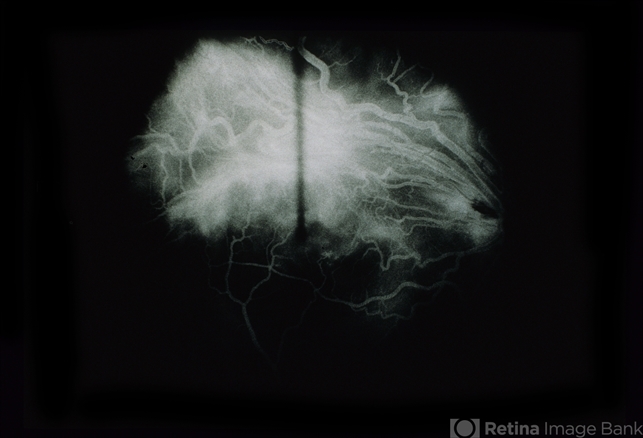

- Von Hippel Lindau Disease (VHL) Case 2

- Von Hippel-Lindau

- 30 year old woman with confirmed von Hippel-Lindau disease.